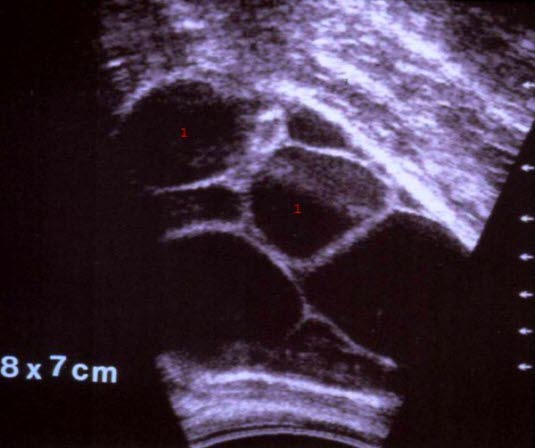

Theca-lutein cyster

1. Cystecaviteter